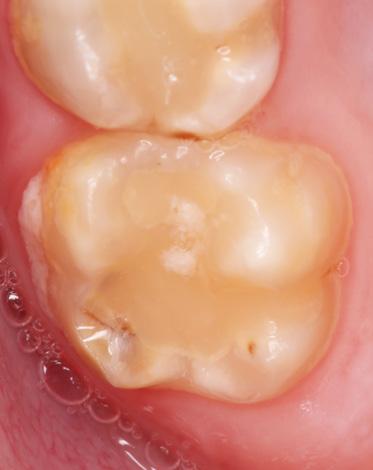

Für die Diagnose einer MIH ist der klini sche Befund entscheidend. Kriterien zur Erfassung der hypomineralisierten Zähne liegen von der EAPD vor [14], die wie folgt festgelegt sind: klar umschriebene Opazi täten (Abb. 1, 2), posteruptive Schmelzab brüche (Abb. 1), atypische Restaurationen (Abb. 3) und atypische Extraktionen. Diffe rentialdiagnostisch müssen u. a. folgende Krankheitsbilder in Betracht gezogen wer den: Fluorosen, erbliche Strukturanoma lien (Amelogenesis imperfecta) und exogen bedingte Defekte (Trauma, Turnerzahn, Karies).

Abb. 1: MIH an den Zähnen 16 und 26. Zahn 16 weist bereits einen posteruptiven Schmelzeinbruch im distalen Bereich auf, Zahn 26 zeigt abgegrenzte Opazitäten. Abb. 2: Patientin aus Abb. 1. Die beiden mittleren oberen Inzisiven zeigen jeweils eine umschriebene Opazität.

Abb. 3: Atypische Restauration bei einem von einer MIH betroffenen oberen Molar. Im Randbereich der Füllung sind Opazitäten erkennbar.